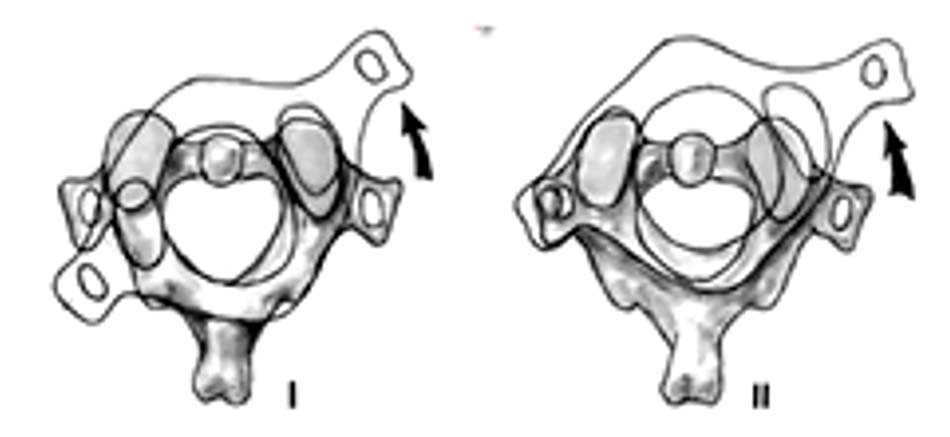

Dựa trên hình ảnh Xquang, cắt lớp vi tính và cơ chế tổn thương, Fielding chia trật C1-C2 thành 4 loại [42]:

- Loại 1: trật nhẹ diện khớp, ADI < 3mm.

- Loại 2: đứt dây chằng ngang, ADI: 3 – 5 mm.

Hình 1.28. Trật C1-C2 loại 1 và 2 - Loại 3: đứt dây chằng ngang, dây chằng cánh, ADI > 5mm.

- Loại 4: trật C1 ra sau so với C2, thường phối hợp gãy mỏm nha hoặc vỡ cung trước C1.

Hình 1.29. Trật C1-C2 loại 3 và 4